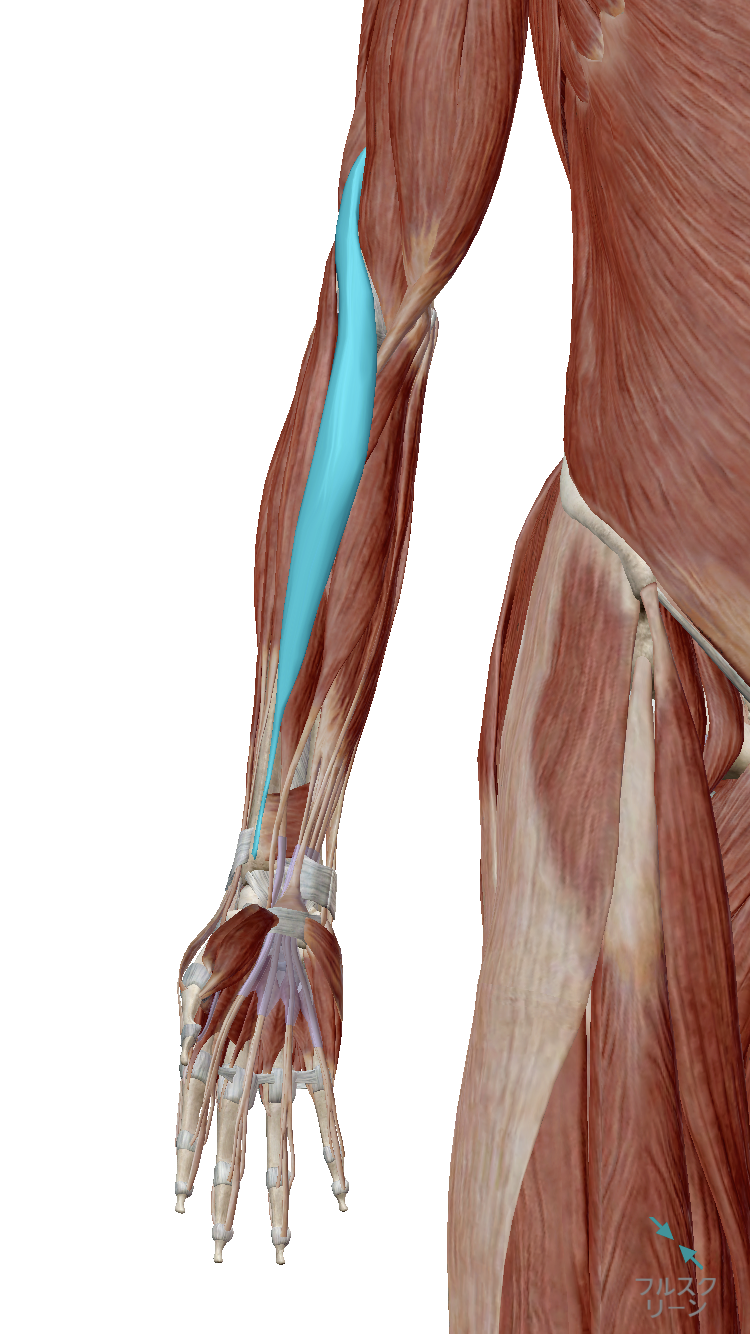

腕橈骨筋を正しく図で理解しよう。理学療法士・作業療法士・言語聴覚士の求人、セミナー情報なら POST。

腕橈骨筋の起始・停止・支配神経 brachioradialis 暗記用画像付き徹底的解剖学 かずひろ先生 解剖学。

腕橈骨筋│clindsc。

腕橈骨筋高津整体院。

腕橈骨筋 – いつでも何回でも再学習☆応援講座。